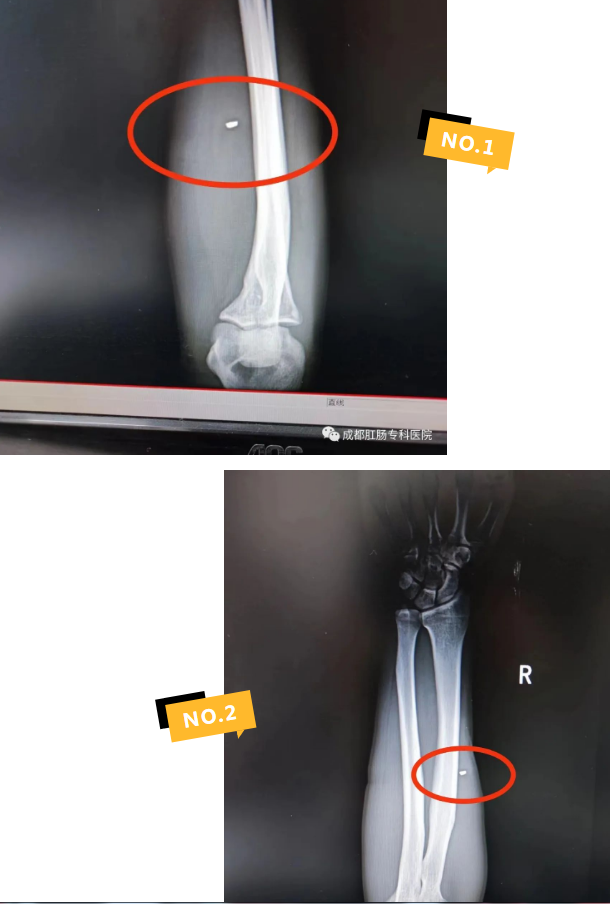

到了医院,首先要解决的问题是,先确定铁销在肌肉中的位置,然后再将迸进肉里的铁销取出。经过放射科透视检查,在患者王磊的右臂中发现一块长为4毫米、直径不到2毫米的铁销。

于是,在经过局部麻醉后,在患者王磊的手臂上,孙健主任只开了一个大约2厘米的小创口,然后用吸铁石对着创口一吸,这块铁销立即就被吸出来了,前后总共花了不到两分钟的时间,尽最大可能减少患者损伤。